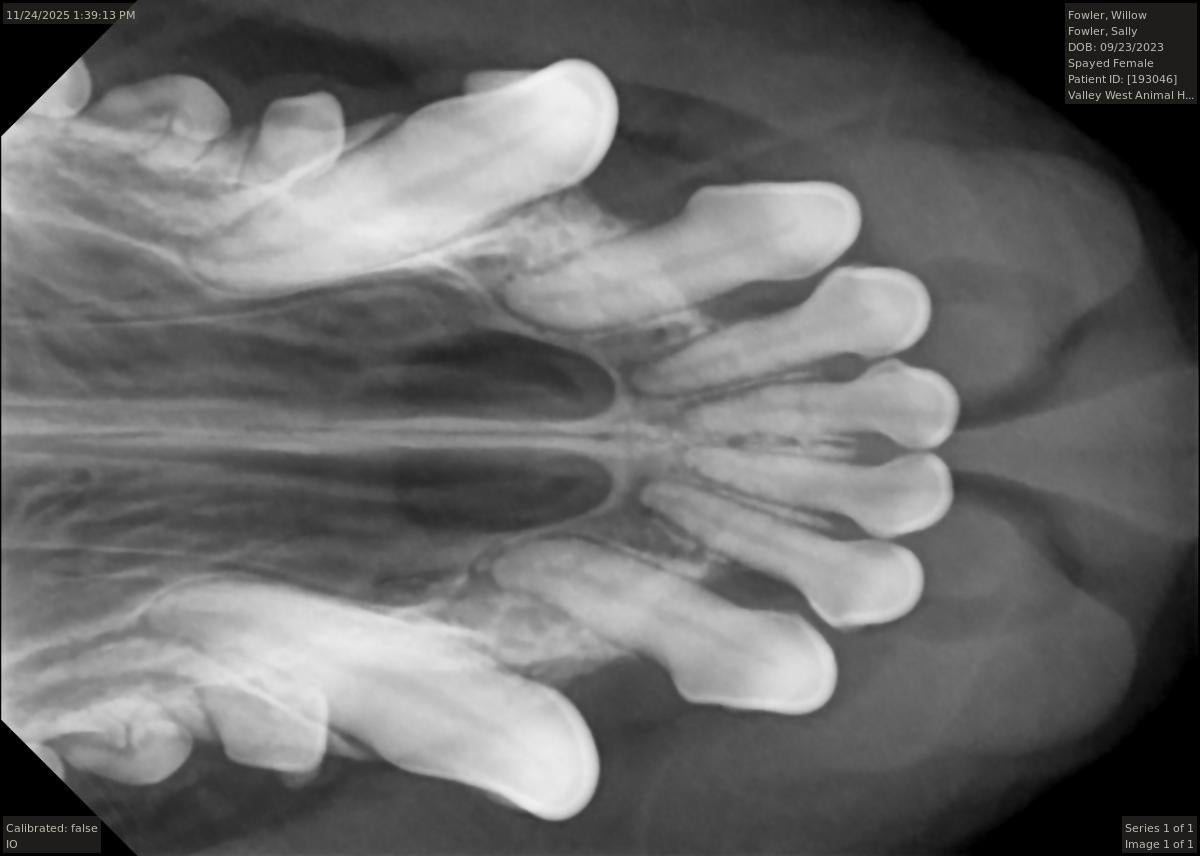

In order to remove this tartar, we perform dental scaling, our most basic dental procedure. During the scaling process our practice uses sonic and ultrasonic power scalers as well as hand held instruments to remove this tartar from the surface of the teeth both above and below the gum line.

Tooth extraction is another very common procedure. It is the goal of our practice for your pet to retain as many teeth as possible. However, sometimes extraction is the only option to relieve pain or ensure that periodontal disease does not advance. If not extracted, many times a diseased tooth can compromise the surrounding tissue and neighboring teeth. If caught early, there are more treatment options available for periodontal disease.